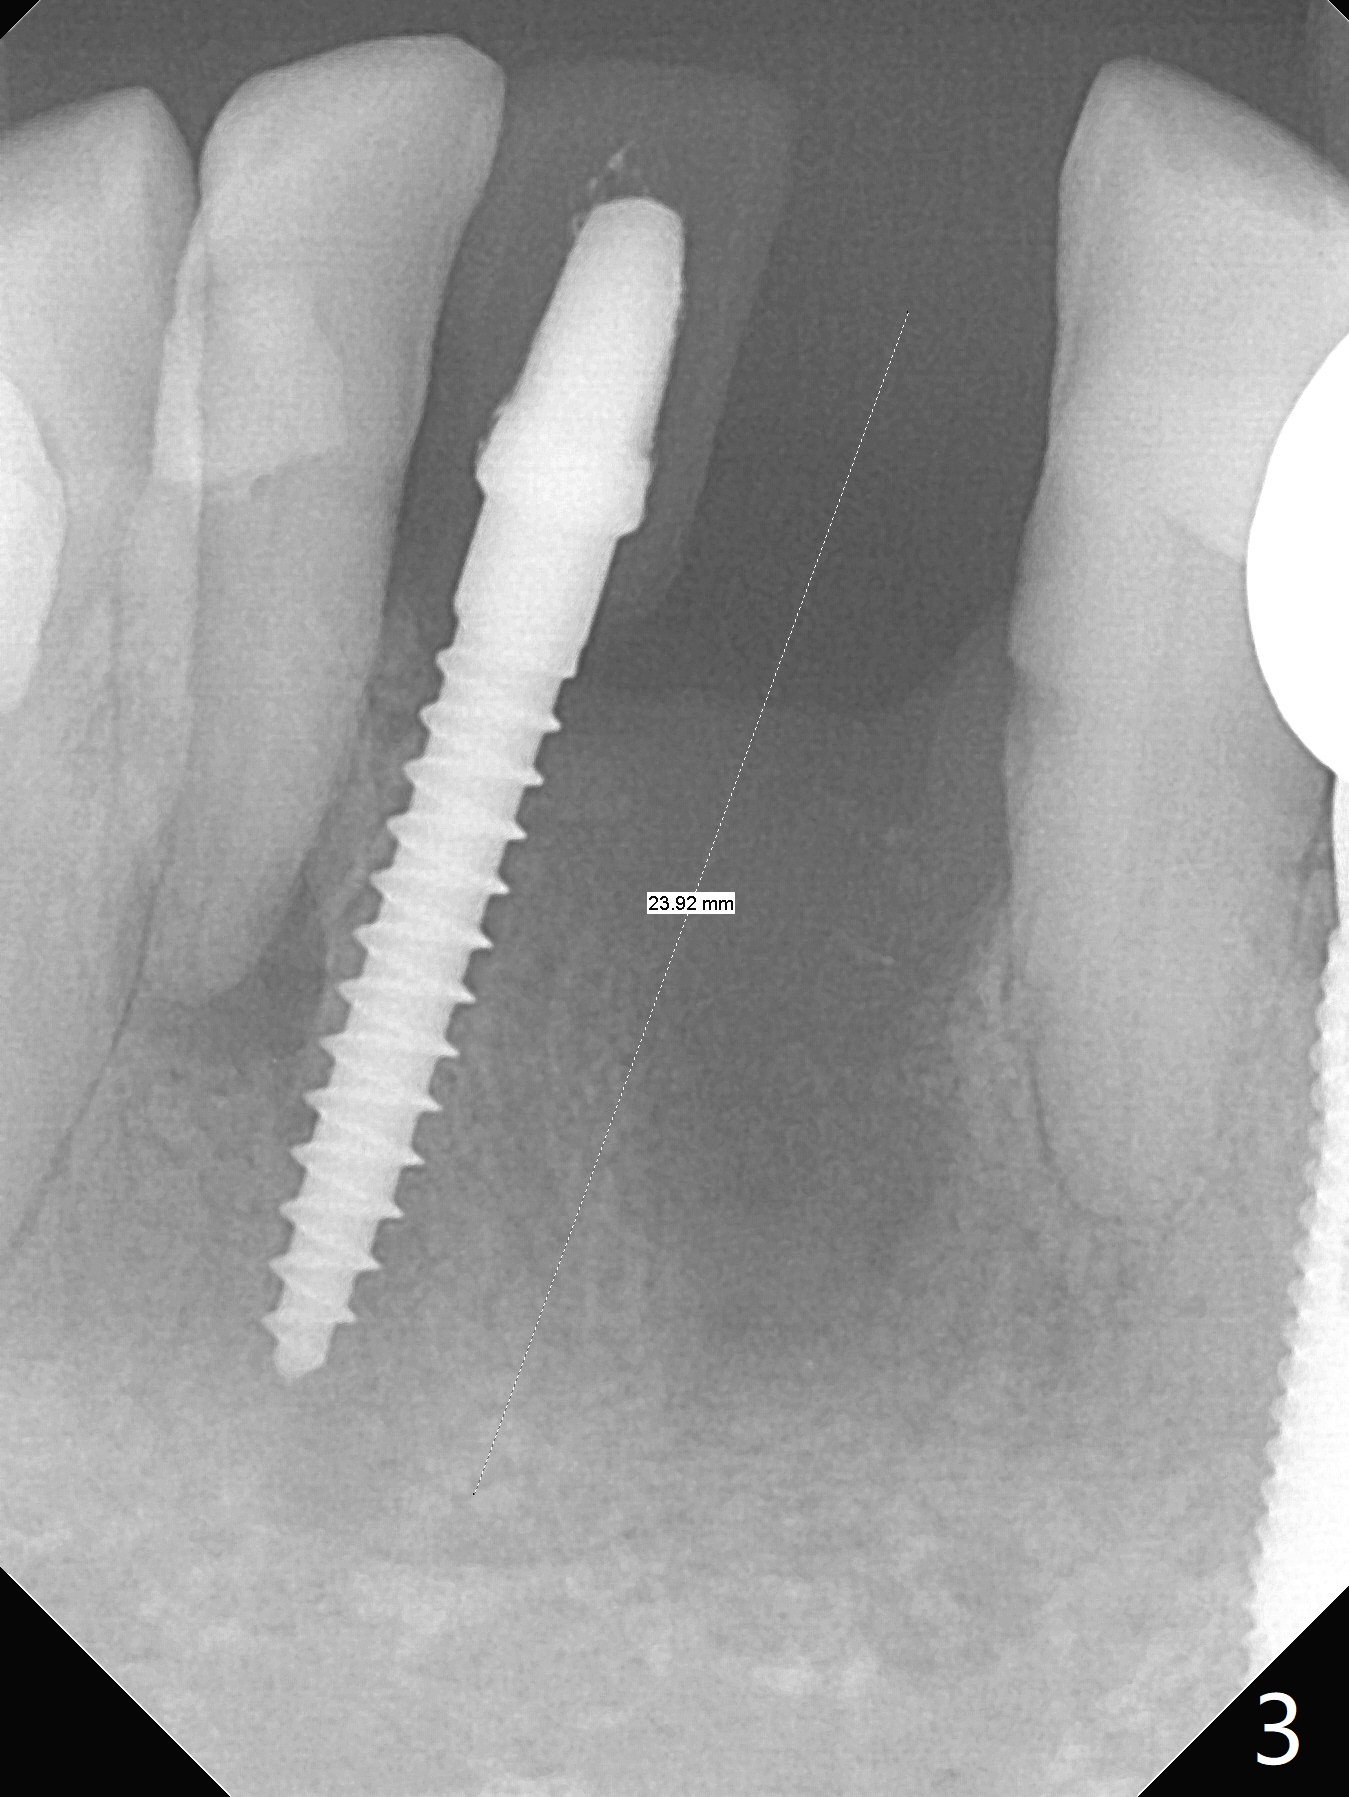

Two and a half months after loss of a 2 mm 1-piece approximately at #23 (Fig.1,2), it appears that the site of #24 (Fig.3 line) is more appropriate because the bone is higher. After removal of the pointed ridge top, osteotomy is initiated with 1.2 mm drill, followed by 1.5 mm one (Fig.4,5). When the 1.5 mm drill is removed, the new osteotomy (Fig.6 *) is mesial to the old one (^). Since the ridge is narrow (Fig.5,6), a 2x14(4) mm 1-piece implant is placed with GBR (Fig.7). Due to overprep, the torque is 20 Ncm. No immediate provisional is fabricated. Instead periodontal dressing is applied around these 2 implants. Two separate provisionals are fabricated when the wound heals. The one at #24 does not stay. The implant at #24 appears to osteointegrate 6.5 months postop (Fig.8). When the crowns are cemented, the margin is supragingival (Fig.9,10). Water Pik is recommended.